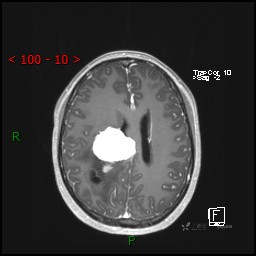

视物模糊发现颅内占位,“豆蔻年华”却承受开颅之痛,所幸一切顺利---结果公布~

患者年龄:14岁

简要病史:患者于1月前无明显诱因出现视物模糊,无明显头痛头晕,无恶心呕吐,无昏迷,无肢体偏瘫等症状,就诊于当地医院头部CT考虑:右侧丘脑、脑室占位。予以对症处置后家属为求进一步诊治来我科,以“颅内占位”收入院。 起病以来,精神、饮食、睡眠欠佳,大小便正常,体力下降,体重无明显变化。

临床诊断:脑室占位

MRI平扫